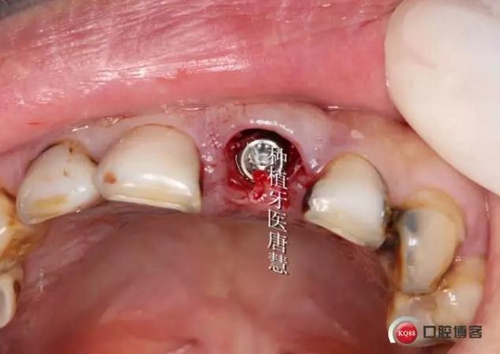

術(shù)前曲斷

1.jpg